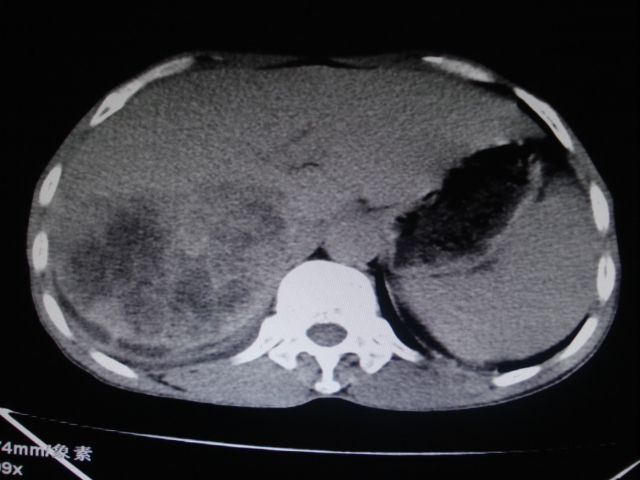

标题: CT24041:肝脏占位,请会诊!

男性,62岁。肝右叶占位,平扫及增强如下,延迟期为15分钟扫描。